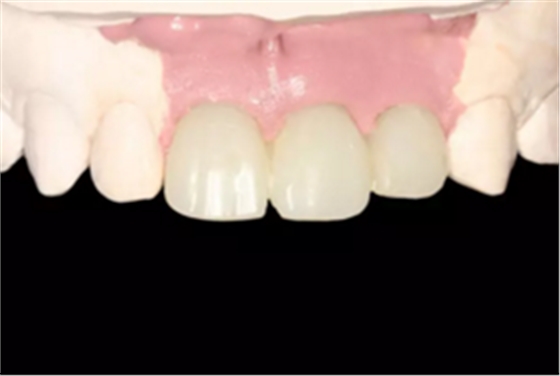

图23 最终修复后即刻口内像

图25 最终修复后复查口内像

(4)最终修复。种植体周围软组织改建成熟以后,进行最终修复。本 病例采用两步法印模技术精确记录种植体的三维位置和种植体周围软组织穿 龈轮廓外形。 首先,口内制取临时冠及周围软硬组织的硅橡胶阴模,复制软硬组织 表面形态。然后,取下临时修复体,常规制取闭窗式种植体水平聚醚印模, 精确记录种植体的三维位置,灌制含人工牙龈的超硬石膏模型。最后,去除 模型上的人工牙龈,将临时修复体戴入到模型上,在临时修复体周围和硅橡 胶阴模内注入人工牙龈,将阴模就位到含临时冠的石膏模型上,精确转移穿龈轮廓外形,获得工作模型。 制作螺丝固位的一体化氧化锆基台冠,以切削方式制作完成后,表面 添加饰瓷来获得理想的美观效果。 术后7个月,戴入最终修复体,红白美学效果满意。

(5)复查。种植体周围骨水平稳定,龈乳头及龈高点位置稳定,龈缘 曲线形态理想,唇侧软硬轮廓良好,功能满意,修复效果符合预期。